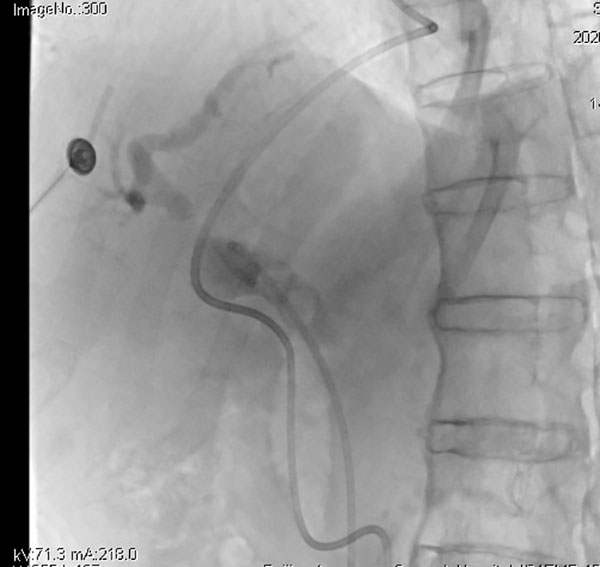

春节期间,我院心血管内科团队共完成19台冠状动脉造影,其中8台为介入治疗。他们用专业与担当,守护着每一颗跳动的心脏,让生命之花在寒冬中绽放。

马年春节假期,北京航天总医院消化内科副主任张波带领ERCP(内镜逆行胰胆管造影术)团队,为一名辗转多家医院就诊的胆总管多发结石、胆道梗阻患者进行ERCP胆管引流术,守护了患者的生命与健康。

大年初三下午16时,消化内科副主任张波接到普外科门诊崔校航医生的电话:一位老年男性,1天前因腹痛辗转于北京市3家三甲医院,完善相关检查后诊断胆总管多发结石、肝内外胆管扩张、胆囊多发结石,由于春节假期等多种原因,三家医院当前均不能行ERCP手术,患者和家属又赶往我院寻求进一步治诊治。胆道梗阻对消化内科和普外科医生并不陌生,胆总管是胆汁流入肠道的唯一通道,一旦发生阻塞,会迅速引发急性化脓性胆管炎、感染性休克,严重时可危及生命。张波副主任电话中与患者家属交代病情后,一边驱车赶往医院,一边联系消化内科值班医生陈帝副主任医师立即将患者收入院,给予抗炎、补液同时完善术前检查,并提请麻醉科会诊为ERCP手术做准备,麻醉科许军副主任医师很快到达床旁会诊评估,根据患者病情补充了术前检查和其他相关科室会诊。张波副主任到院后,仔细查体、阅片后将患者病情向邸雅南主任汇报,鉴于患者基础疾病较多,两位专家一致认为应先行ERCP解除梗阻、引流胆汁,治疗方案得到患者和家属的认可。

次日上午,ERCP团队成员李文杰护士赶往医院完成术前准备,麻醉科孔文靖主治医师和护士赵悦现场保驾护航,张波副主任进镜、插管、造影、留置鼻胆引流管一气呵成,——一场消化科、麻醉科、普外科无缝衔接、紧密合作的胆道梗阻的救治,在短时间内成功完成。术后,患者很快从麻醉状态中苏醒,腹痛症状立刻得到缓解,胆汁引流通畅,但这只是第一步,考虑到患者合并胆囊多发结石,后续治疗需要胆道梗阻多学科会诊讨论,以制定使患者最大化获益的治疗方案。

北京航天总医院消化内科ERCP团队,以“一切为了大众健康”为使命担当,畅通急诊ERCP绿色通道,他们不仅技术精湛,更注重以人为本的治疗理念,在决定治疗方案时,始终将患者的生活质量和长远健康放在首位,更以细致入微的全程管理守护生命质量:术前精准评估、术中动态决策、术后多学科随访,让每一次胆道介入都成为一次有温度的生命托举,以敬畏生命的态度,在每一次插管、每一帧造影、每一根引流管的留置中,践行着对健康最朴素的承诺。更以始终如一的坚守,在万家团圆时奔赴生命一线,在毫厘胆道间倾注千钧仁心。此刻,是医者以专业为笔、以仁心为墨,在生命最幽微的通道里写下的新春贺词。